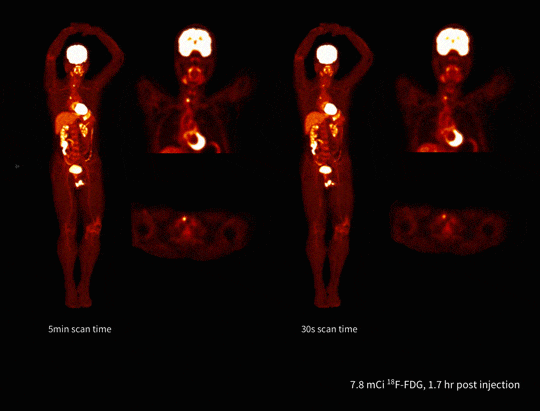

Imagistică total-body rapidă

uEXPLORER permite scanări PET/CT ale întregului corp în doar 30 de secunde, evidențiind clar chiar și leziuni precum nodulii tiroidieni cu absorbție ridicată. Viteza crescută îmbunătățește confortul pacientului și reduce artefactele de mișcare.

Imagistică PET/CT cu doză redusă de radiotrasor